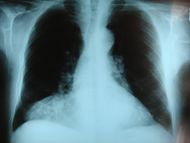

Hernia de Morgani.JPG

Frontal chest X-ray showing a hernia of Morgagni